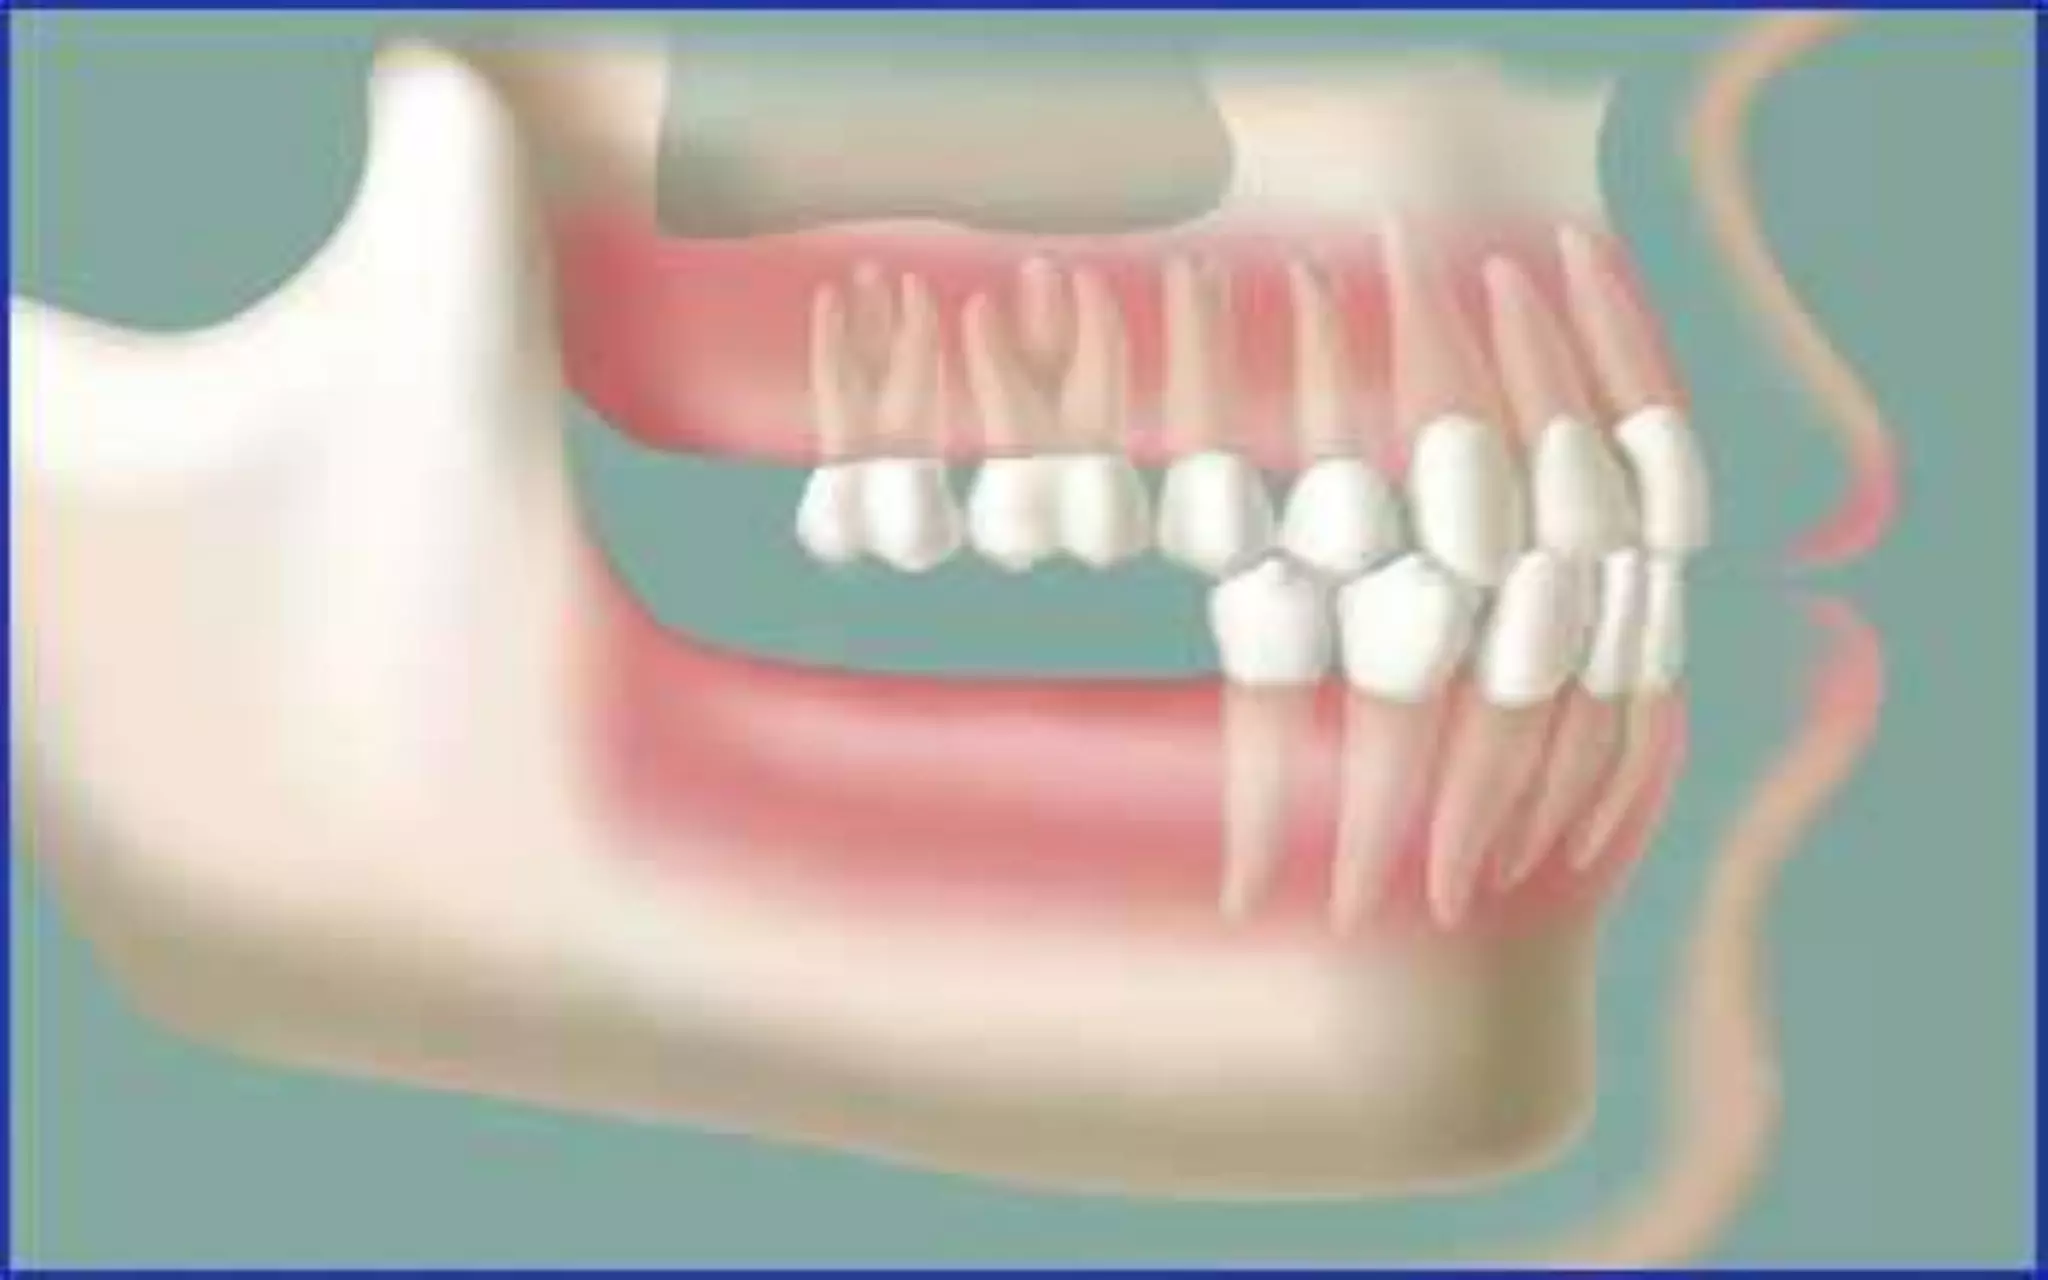

What are the consequences of tooth loss?

• Without the stimulation of the tooth or root the above

become unused &continuously resorbs.

•When a tooth is lost , the lack

of stimulation to the residual

bone causes a decrease in

trabeculae and bone density

in the area, with loss in

external width, the height, of

the bone volume

•With top premolars missing and

premolars have no opposing force

so they continue to erupt

•With no posterior contact all the

force is placed on anterior teeth

which in turn are overloaded and

pushed forward and outward

•Clinical example of side view